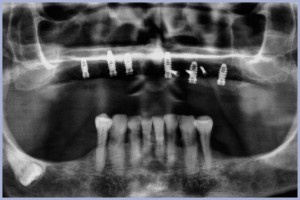

La paziente di sesso femminile ex fumatrice, di anni 78, si presenta alla nostra osservazione con una situazione di edentulia dell’arcata superiore di vecchia data e di conseguenza con una grave atrofia ossea sia orizzontale che verticale (Fig. 1), chiedendo una riabilitazione protesica fissa.

L’ortopantomografia di controllo immediata conferma la buona riuscita dell’intervento (Fig. 40).

- Fig. 1

- Fig. 40